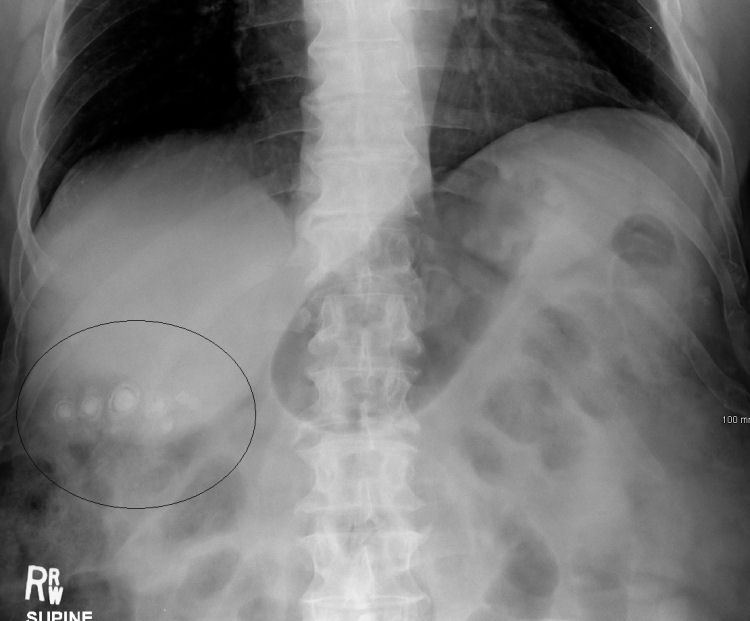

back Gall stones as seen on plain X-ray

Source: StonesXray.PNG

Author: James Heilman, MD